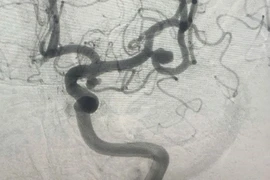

Người phụ nữ 47 tuổi sau khi tắm đột ngột đau đầu dữ dội kèm nôn ói vì xuất huyết dưới nhện do vỡ túi phình mạch máu não. May mắn, bệnh nhân được các bác sĩ cứu sống kịp thời.

Sau tắm hôn mê do vỡ túi phình mạch máu não